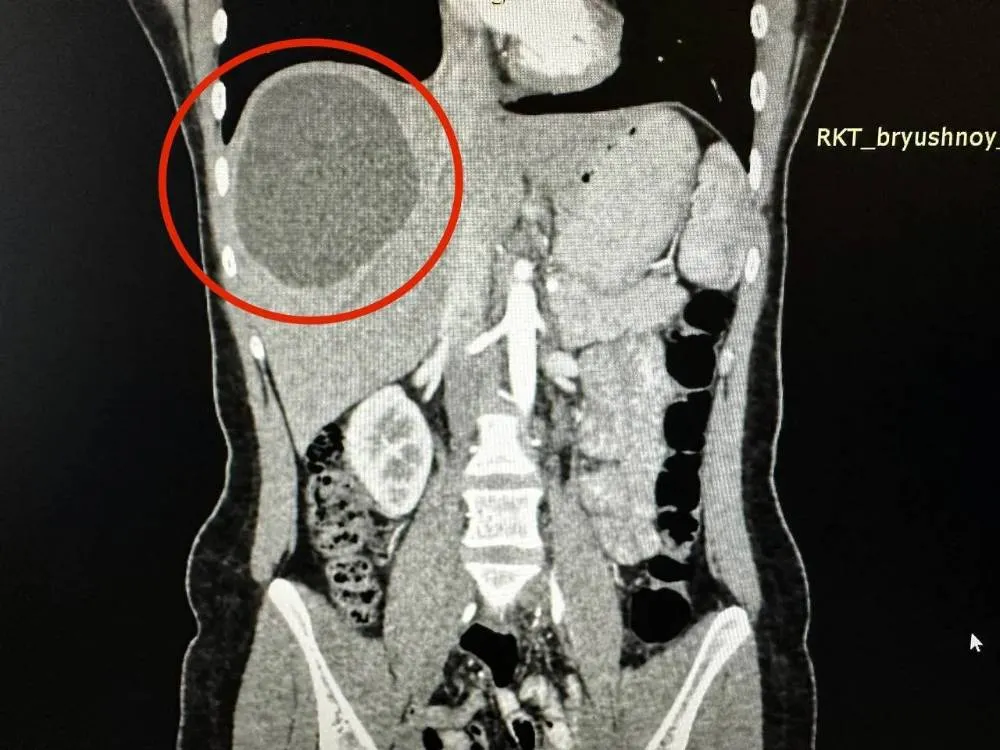

По информации сотрудников больницы, девушка обратилась за помощью из-за сильных болей в животе. Специалисты обследовали пациентку, обнаружив в её печени ком червей-паразитов, образовавших кисту 20 на 15 см.

"Медики назначили девушке лечение лекарственными препаратами, чтобы убить паразитов. А через три месяца пациентка легла на операцию в отделение хирургии № 2 РКБ. Черви поразили здоровые ткани печени, поэтому хирургам пришлось убрать практически 1/3 органа", — говорится в сообщении.